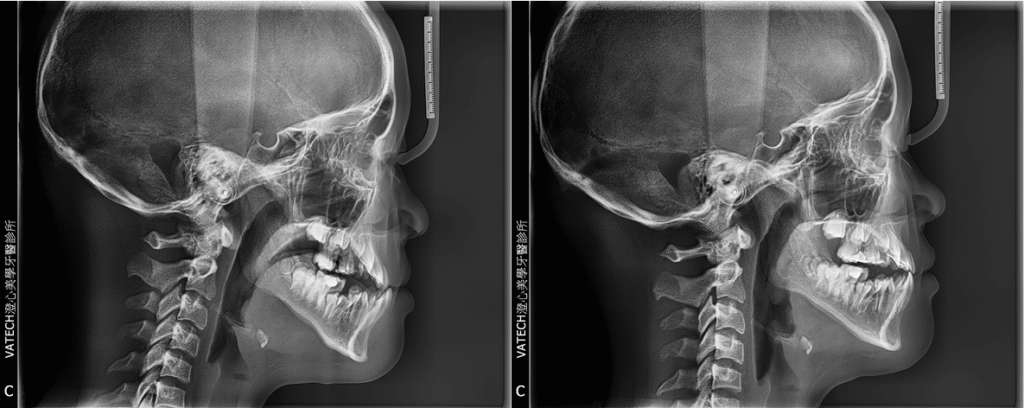

FA MARS 快速擴弓|矯正案例

我們來看看以下這個案例

矯正前屬於「前牙骨性反咬」也就是俗稱的(地包天)

而我們利用「快速擴弓」後,僅僅「一個半月」就將上顎骨拉寬,使得原本”戽斗” 因為上顎變寬+往前拉,變回了正確了位置。

接著,我們只要幫因為拉寬的”牙齒縫隙”利用牙齒矯正就能夠回到相對的位置。